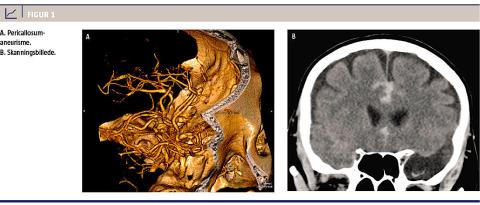

han akut indlagt på en neurokirurgisk afdeling til

behandling for en SAH fra et højresidigt pericallosumaneurisme (Figur 1). Symptomerne herpå var pludseligt indsættende svær nakkehovedpine uden bevidsthedstab. En CT viste SAH i de basale cisterner og henover corpus callosum uden hydrocefalus. Forløbet i neurokirurgisk regi var vellykket med operativ klipsning af aneurismet. En kontrol-CT viste følger efter højresidig klipsning og efter et mindre frontalt infarkt på højre side i tæt relation til den indsatte klips. Patienten blev udskrevet uden sequelae og uden psykiatriske symptomer. Han blev siden fulgt i et psykiatrisk ambulatorium i 15 måneder og var under hele forløbet i fuld klinisk remission. Han fortsatte hos egen læge, hvor han blev behandlet med lamotrigen 200 mg dagligt. Han var fortsat symptomfri fire år efter insultet.